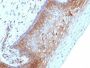

HL-60 or HeLa cells. Melanomas and Lymphoma. Carcinoma of Stomach, Cervix, Endometrial, Kidney or Colon.

Flow, intracellular (verified)|IF (verified)|IHC, FFPE (verified)|WB (verified)

Higher concentration may be required for direct detection using primary antibody conjugates than for indirect detection with secondary antibody|Immunofluorescence: 0.5-1 ug/mL|Immunohistology formalin-fixed 0.5-1 ug/mL|Staining of formalin-fixed tissues requires boiling tissue sections in 10 mM citrate buffer, pH 6.0, for 10-20 min followed by cooling at RT for 20 minutes|Flow Cytometry 0.5-1 ug/million cells/0.1 mL|Optimal dilution for a specific application should be determined by user